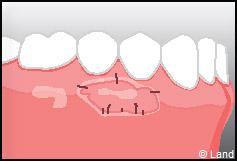

Les greffes de conjonctifs enfouis :

Destinées aux zones esthétiques, elles consistent à prélever la partie profonde du palais (site donneur).

Ce greffon est ensuite inséré sous la gencive au niveau de la récession (site receveur).